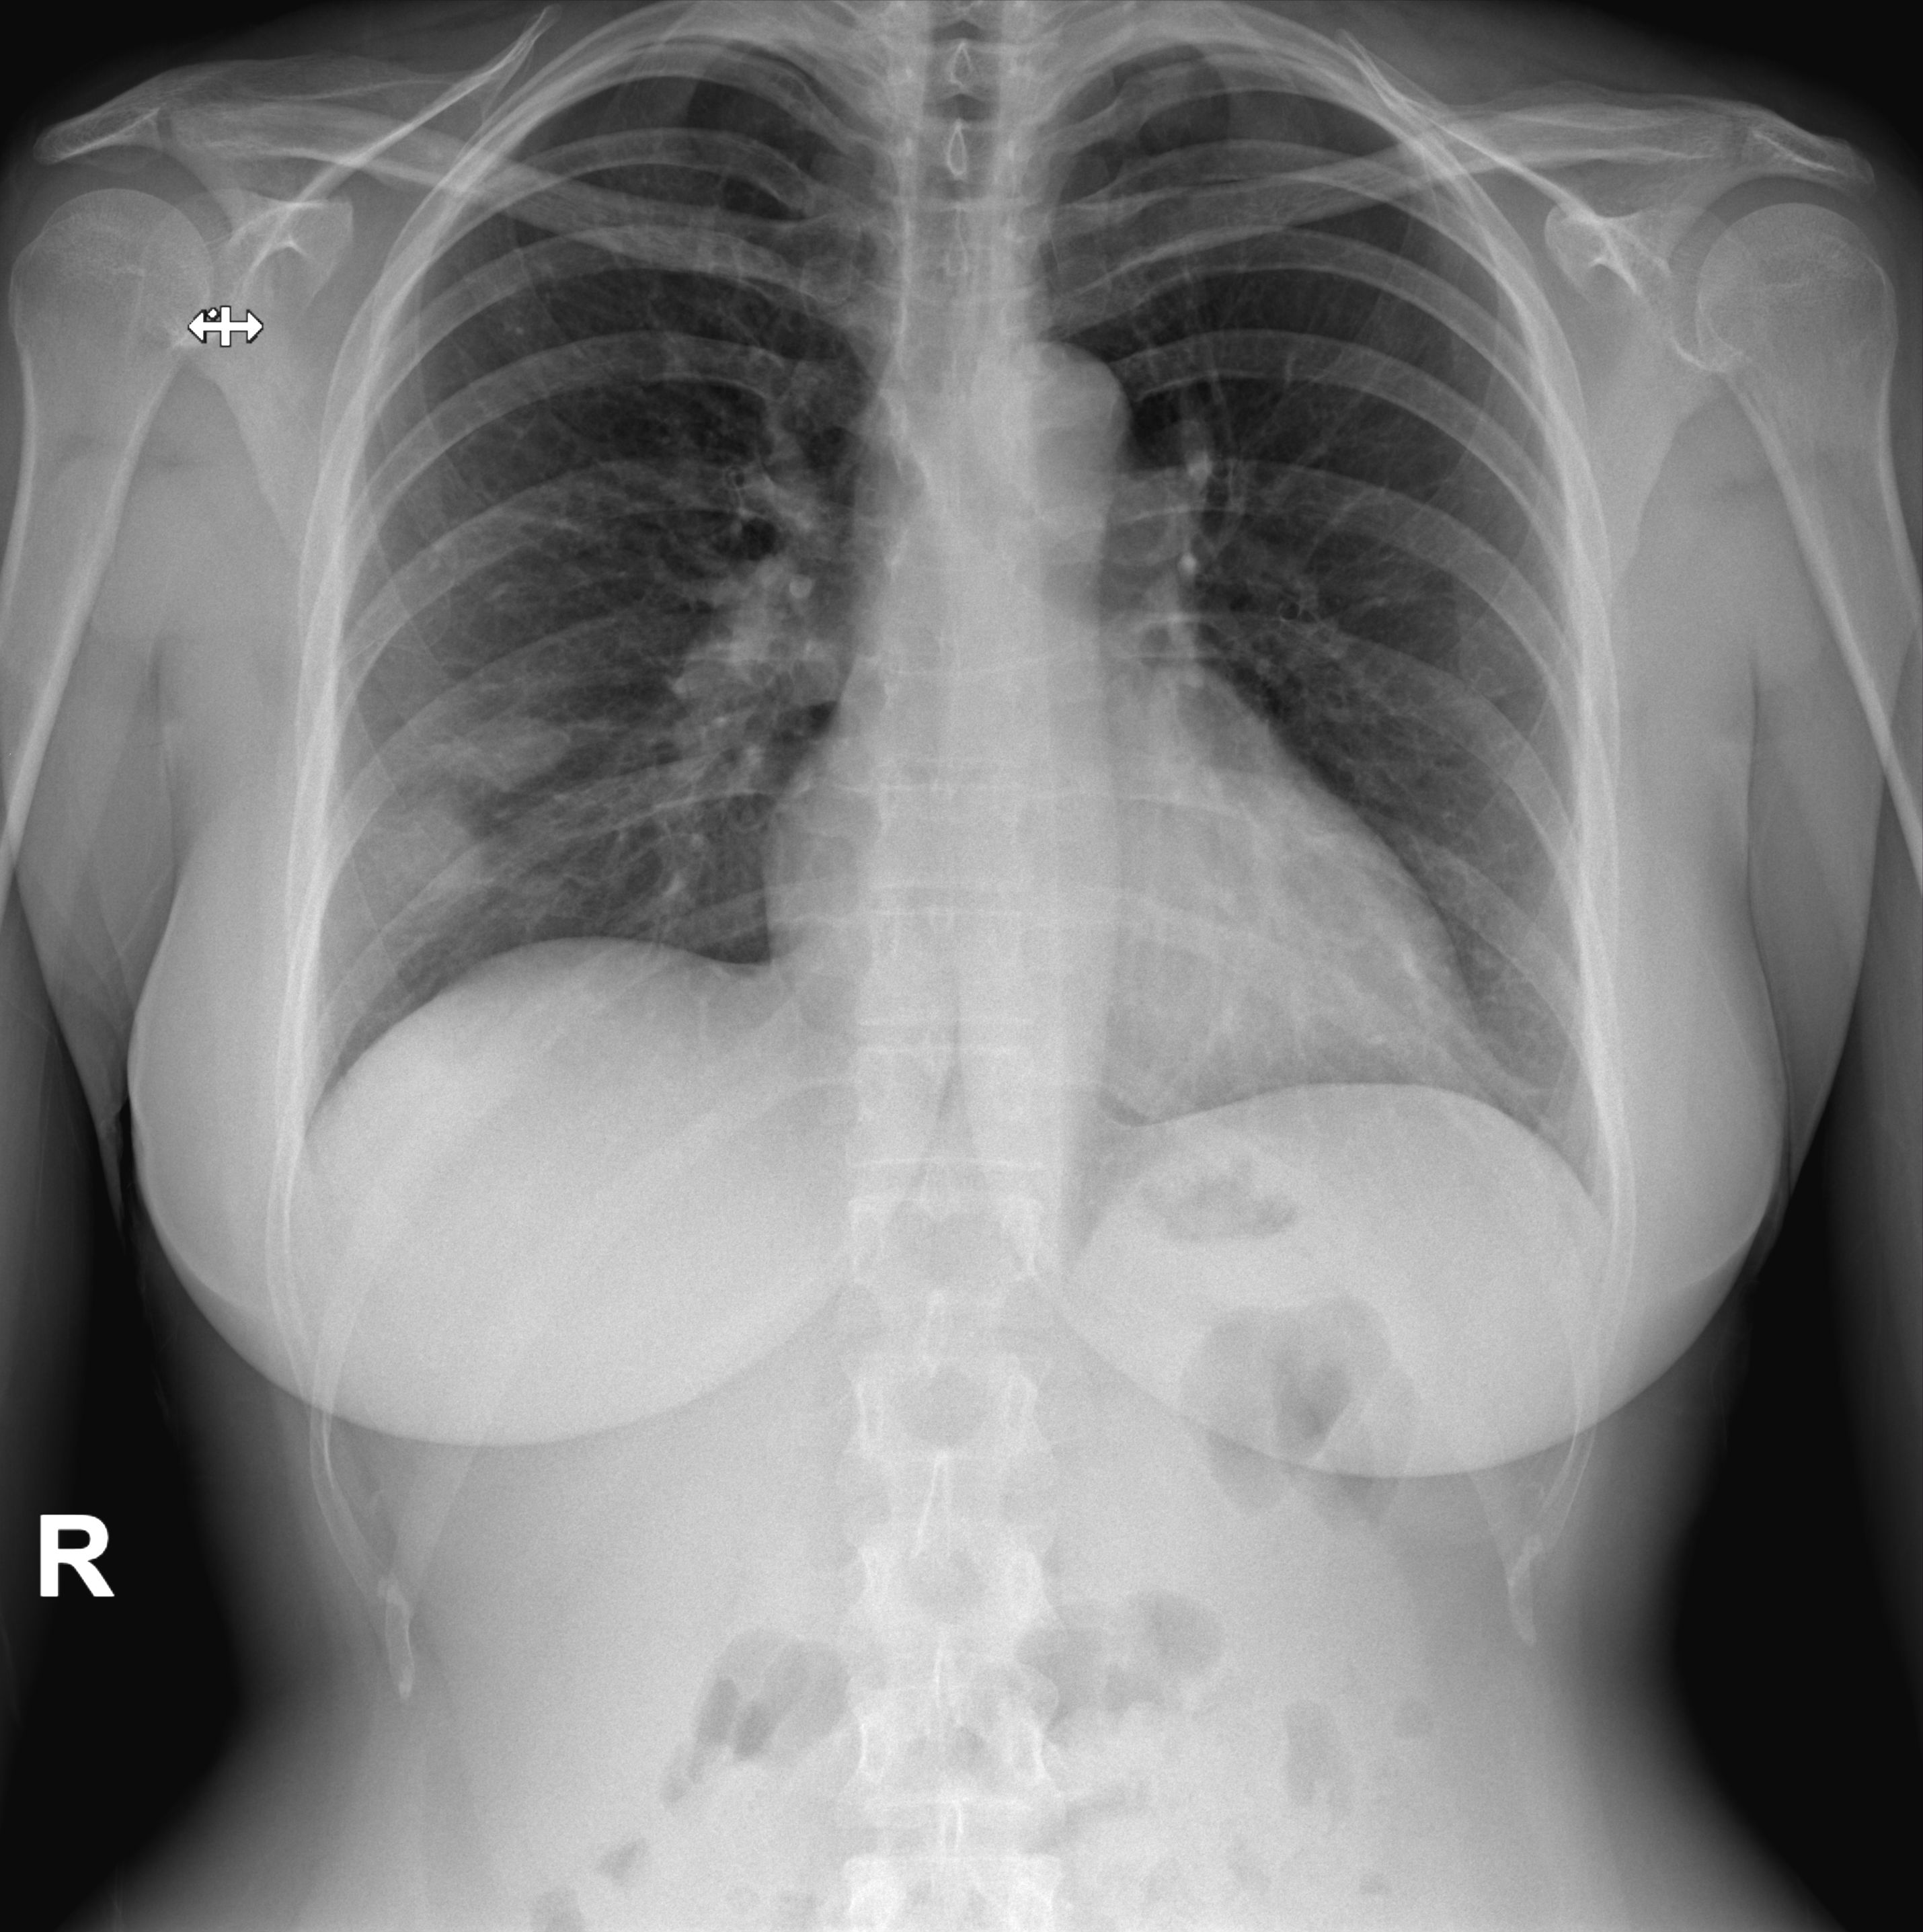

• Rx tórax: Presencia de dos imágenes hipodensas en parénquima pulmonar derecho (LID). No derrame pleural.